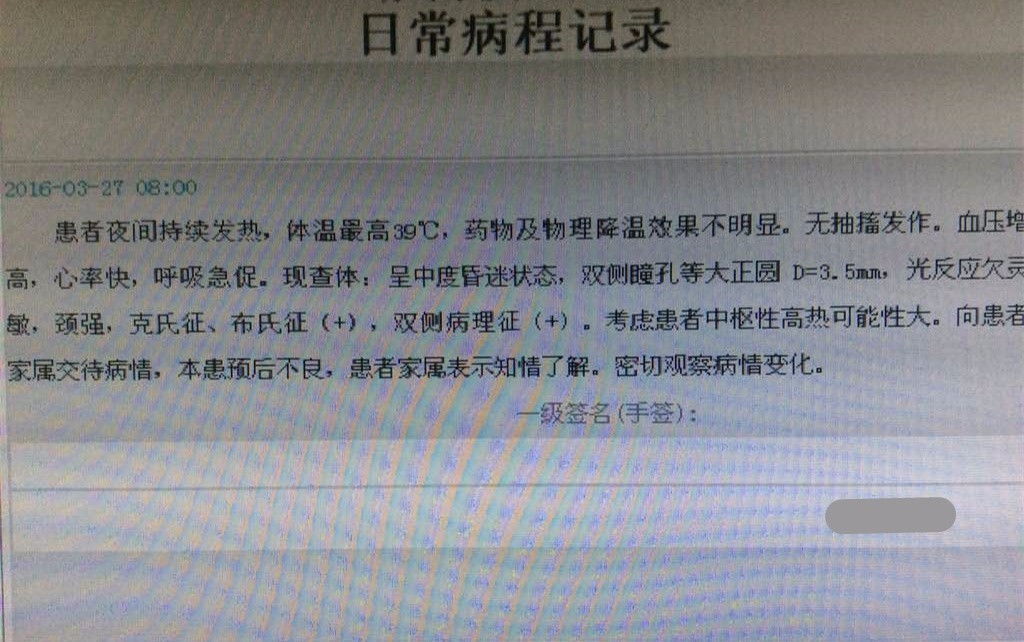

现病史:患者于入院1天前无明显诱因由家属发现头痛,头痛性质及部位不能提供,家属诉其头痛难以耐受,伴恶心、未呕吐,随后逐渐出现烦躁不安、胡言乱语等情况,不能听懂及理解他人谈话内容,无肢体活动不灵,无意识丧失及二便失禁,未予以重视,患者上述症状持续无缓解。入院6小时前患者无明显诱因出现发作性肢体抽搐,家属诉当时患者意识不清,双上肢屈曲、双下肢伸直,头向左侧偏斜,双眼上视、牙关紧闭、口吐白沫、小便失禁,患者肢体抽搐持续约10分钟自行停止,抽搐发作后仍烦躁不安、胡言乱语,再发后未予以任何处置,急来我院,行头颅CT示左额叶低密度影,急诊以“头痛、精神行为异常原因待查”收入我科。患者自发病以来,精神行为异常,饮食睡眠差,大小便正常。

查体:生命体征平稳,意识模糊,双瞳孔正大等圆,光反射灵敏,余脑神经查体欠合作。四肢肌力、肌张力检查欠合作,双侧腱反射存在对称,感觉运动查体欠合作,双侧病理征(+)。颈抵抗。